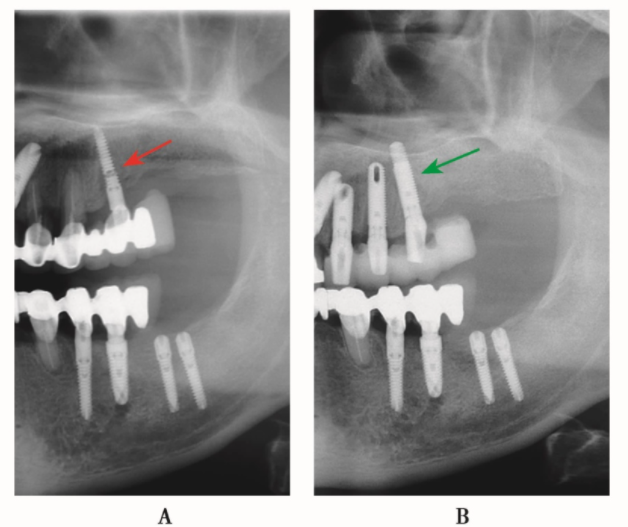

图12 全景片局部A.种植体折断(箭头);B.第二次重新植入直径较粗的种植体